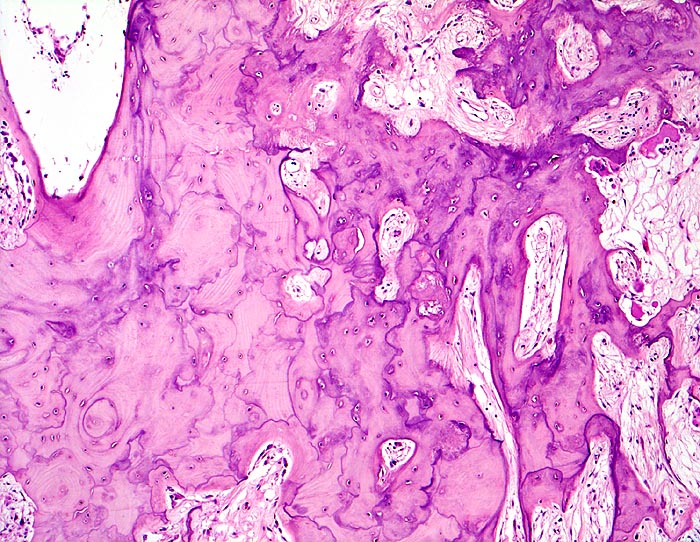

PathoPic – image database / PathoPic ID 4506 - Morbus Paget des Knochens

Morbus Paget des Knochens

Knochen, Tibia

Verbreiterte unregelmässig geformte Spongiosabälkchen mit mosaikartig verlaufenden Kittlinien. Markfibrose. Auffallend grosse Resorptionslakunen mit grossen Osteoklasten.

Für die histologische Diagnose eines Morbus Paget sind folgende Strukturen entscheidend:

Riesenosteoklasten mit mehr als 12 Zellkernen pro Osteoklast

grosse Resorptionslakunen

stimulierte Osteoblasten

milde Endostfibrose

girlandenartig verlaufende Kittlinien